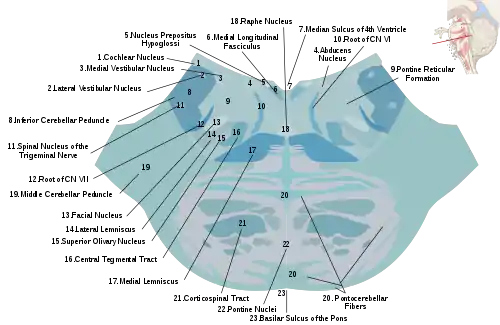

Horizontal section through the lower part of the pons. The central tegmental tract is labeled #16.

Horizontal section through the lower part of the pons. The central tegmental tract is labeled #16. Tractography showing central tegmental tract